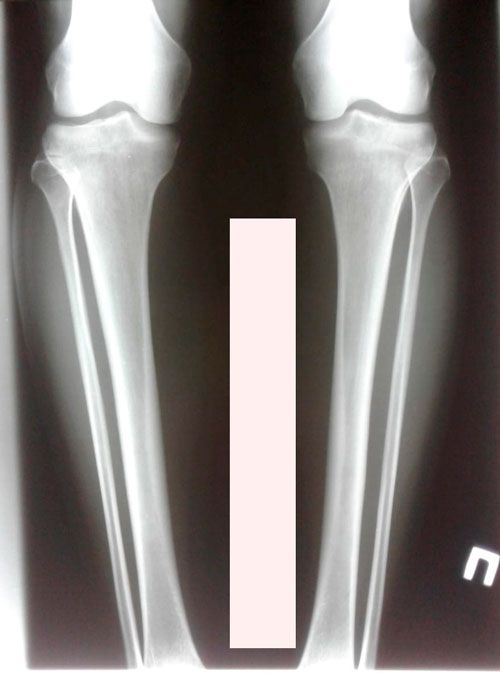

Исходник - 38 лет.Астана.

Дата операции - 12.12.2018г.

Дата снятия аппаратов - 07.03.2019г.

Срок сращения - 82 дня.